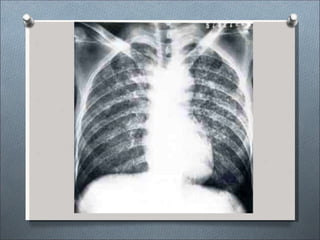

COCCIDIODOMICOSIS

•Enfermedad micótica altamente infecciosa

•Organismo causal: Coccidioides inmitis

•Vía de transmisión: Vía aérea - cutánea

contaminados,

mantienen el

•Fuente de infección: Suelos

Estiércol, roedores infectados

hongo en terreno.

Formas clínicas radiológicas:

•Enfermedad asintomática y tipo gripal.

•Tipo neumónico: Consolidación parenquimal de

lóbulos inferiores.

•Ensanchamiento linfático hiliar o mediastinico.

•Neumotórax.

•Lesiones nodulares con o sin cavitación.

•Lesiones miliares.